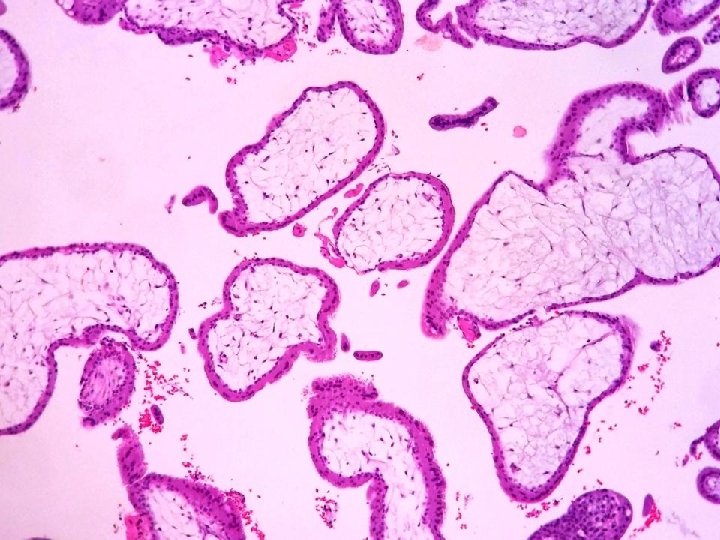

Macroscopía • Pieza de salpinguectomía de 3 x 2 cm de dimensiones máximas con

Macroscopía • Pieza de salpinguectomía de 3 x 2 cm de dimensiones máximas con dilatación de coloración violácea en su porción media. • Fragmentos parduzcos irregulares que agrupados miden 3 x 2 cm

Diagnóstico Anatomopatológico • 1. - Trompa Uterina Derecha (Salpinguectomía) – Malformación Arteriovenosa • 2.

Diagnóstico Anatomopatológico • 1. - Trompa Uterina Derecha (Salpinguectomía) – Malformación Arteriovenosa • 2. - Útero (legrado) – Restos deciduocoriales compatibles con embarazo intrauterino.